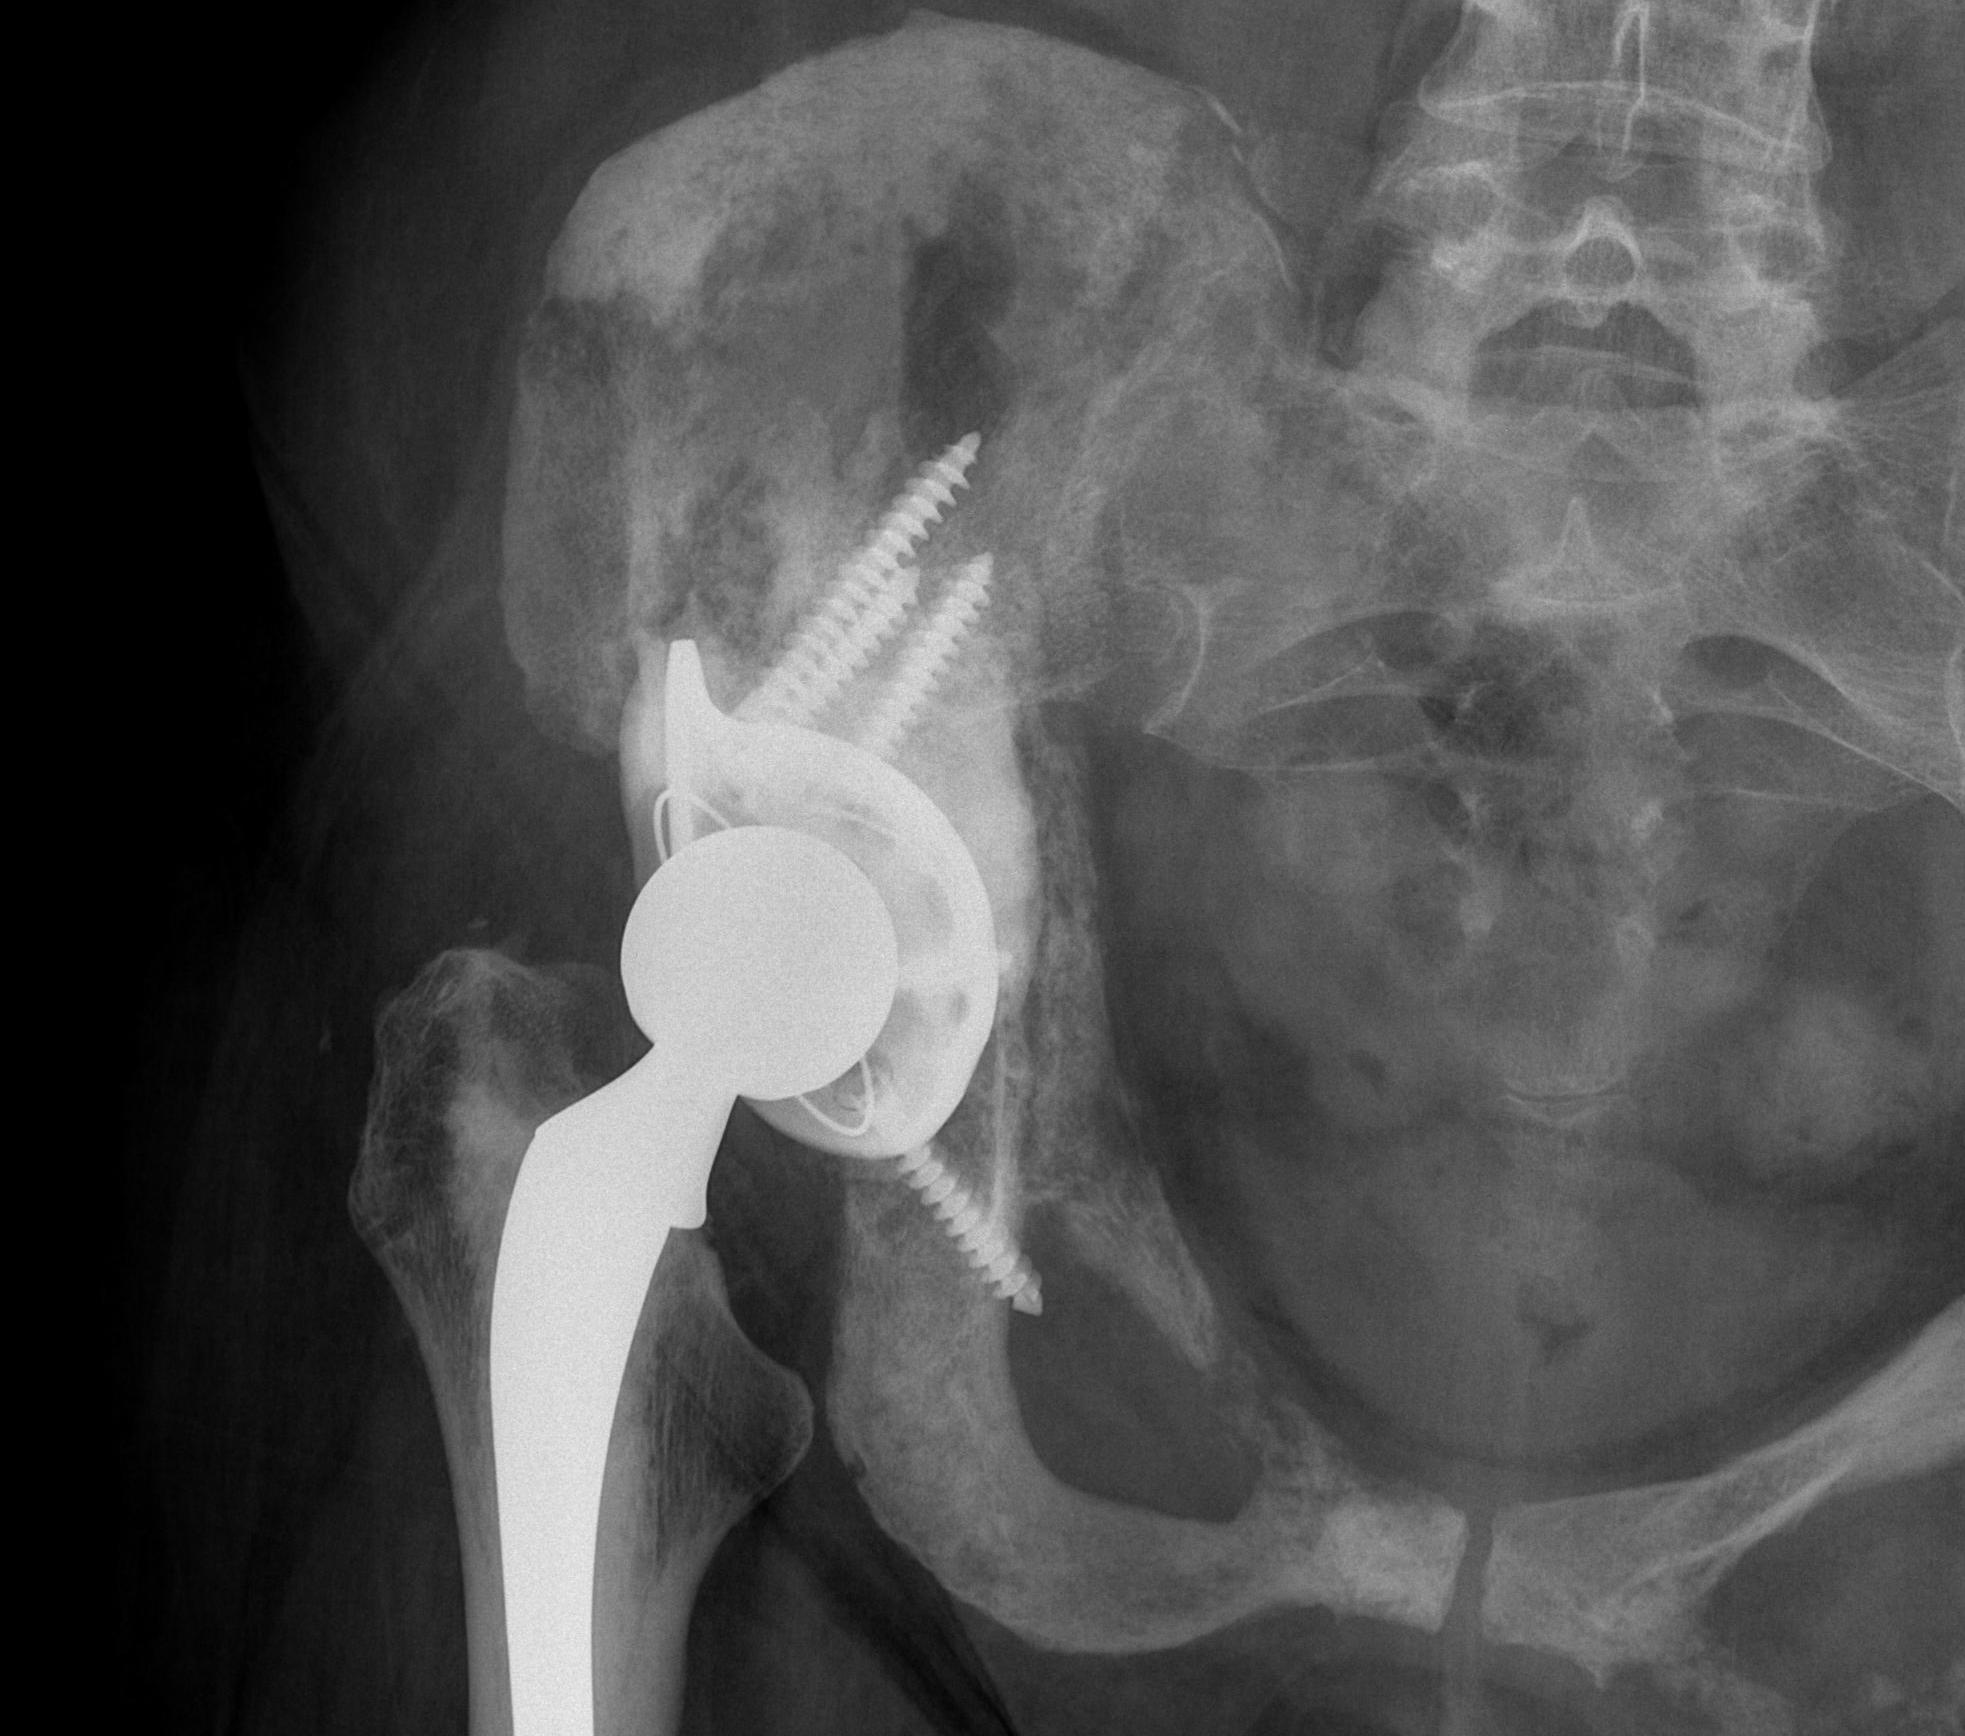

Acetabular Metastasis

Harrington classification

Options

Tantalum augmented cups

Cemented Harrington technique / steinmann pins

Cup-cage

Harrington technique

Cup-cage technique

Results

- 78 patients with Harrington technique versus 37 tantalum acetabular reconstruction

- overall, 21% required additional surgical procedures

- tantalum cups more durable with fewer complications

- cup cage in 47 hips with acetabular metastases

- one patient had loosening due to recurrence 8 years post surgery